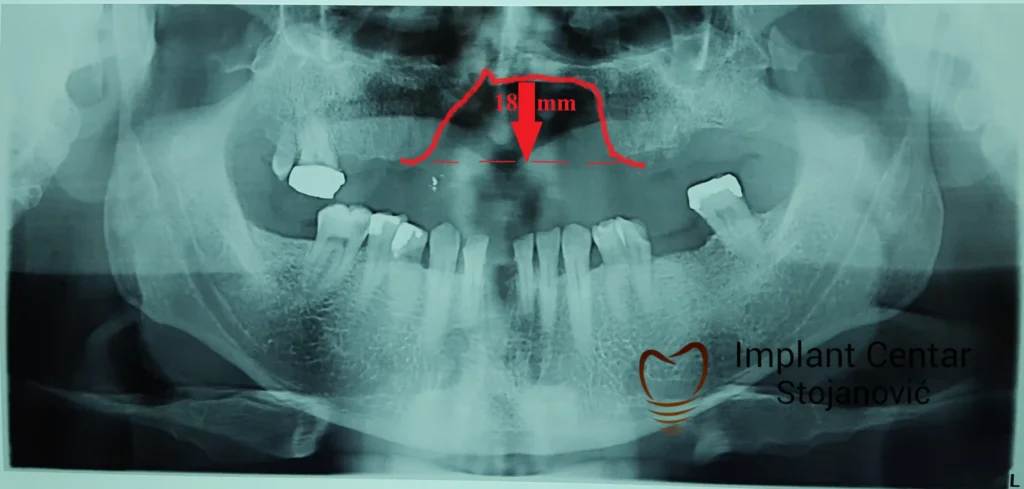

Pacijent sa rascepom usne, nepca i alveolarnog grebena uspešno je rehabilitovan fiksnim protetskim radom na implantatima. Pre dolaska u našu ordinaciju, pacijent je u gornjoj vilici nosio totalnu protezu preko preostalih zuba, dok je u donjoj vilici bio zbrinut parcijalnom mobilnom protezom. Tokom višegodišnje potrage za adekvatnim rešenjem, pacijent nije uspeo da pronađe zadovoljavajuću terapijsku opciju ni u zemlji ni u inostranstvu.

Nakon detaljnog kliničkog pregleda i analize radioloških snimaka, izrađen je sveobuhvatan plan terapije sa ciljem uklanjanja mobilnih proteza i postizanja maksimalne funkcionalne i estetske rehabilitacije. Zbog loše biološke vrednosti preostalih zuba, doneta je odluka o njihovom vađenju i ugradnji dentalnih implantata.

Poseban terapijski izazov predstavljalo je premošćavanje defekta nastalog usled rascepa, kao i ograničena količina raspoložive kosti u gornjoj vilici. Primenom većeg broja implantata i odgovarajućih procedura nadoknade kosti, postignuta je stabilna osnova za fiksni protetski rad.